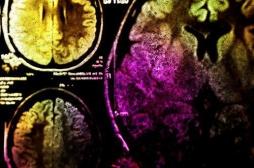

LES MALADIES

SYMPTÔMES